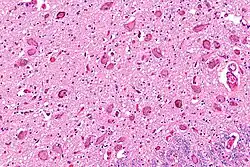

![]() Micrograph showing the locus coeruleus. HE-LFB stain. | |

The locus coeruleus (LC) is located in the posterior area of the rostral pons in the lateral floor of the fourth ventricle. It is composed of mostly medium-size neurons. Melanin granules inside the neurons of the LC contribute to its blue colour. Thus, it is also known as the nucleus pigmentosus pontis, meaning "heavily pigmented nucleus of the pons." The neuromelanin is formed by the polymerization of norepinephrine and is analogous to the black dopamine-based neuromelanin in the substantia nigra.